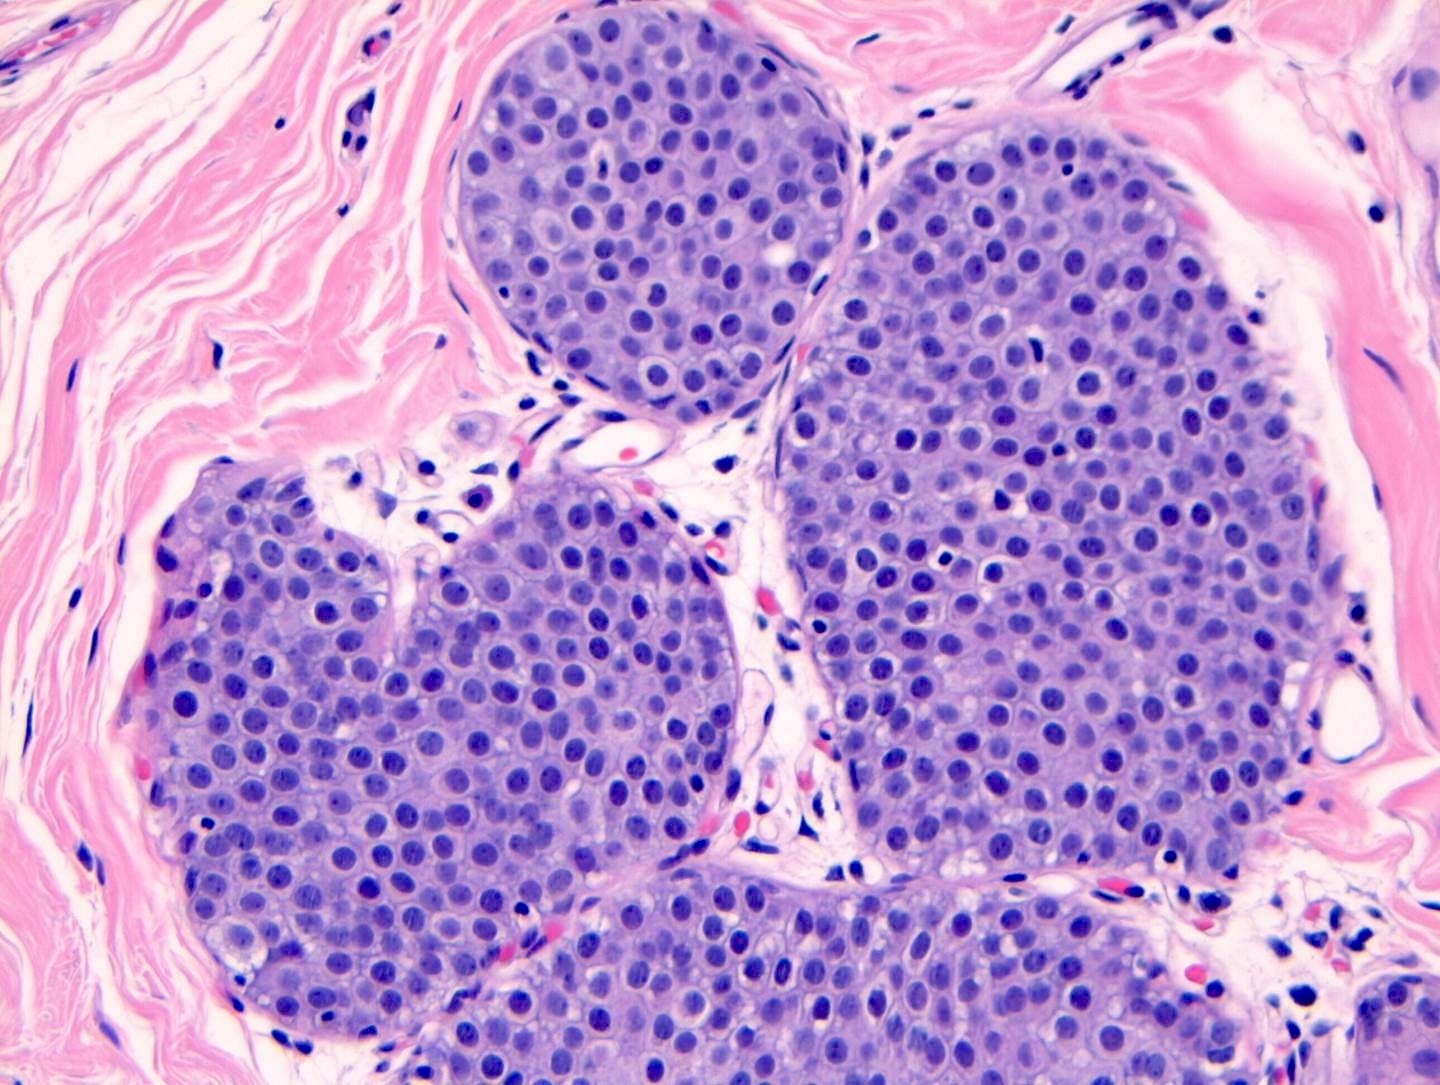

Pleomorphic lobular carcinoma in situ - microscopic images

Precursor of classic lobular carcinoma - pleomorphic lobular carcinoma in situ

Pleomorphic LCIS is a rare (< 5% of LCIS) nonclassical or variant form of lobular carcinoma in situ composed of a noninvasive, neoplastic proliferation of large dyscohesive cells with marked nuclear pleomorphism. Its nuclei are > 4 times the size of a lymphocyte and its cytologic features more closely resemble high grade DCIS than classic LCIS. It may exhibit comedonecrosis and calcifications. However, other features overlap with classic LCIS: loss or dysfunction of E-cadherin, cellular dyscohesion, lack of cell polarity, intracytoplasmic lumina, signet ring cells and pagetoid spread. Most cases are associated with classic LCIS and ALH.

Immunostains for E-cadherin may assist in distinguishing LCIS from DCIS although they must be interpreted in the context of the histologic features.

Pleomorphic LCIS accumulates additional alterations and generally exhibits greater genomic instability than classic LCIS.

Pleomorphic LCIS has features of a high risk precursor lesion of invasive carcinoma. It is associated with a high incidence (49%) of associated invasive carcinoma either on core needle biopsy or excision. Treatment consists of surgical excision but there is no consensus on requiring negative margins, adjuvant treatments or sentinel node biopsy.